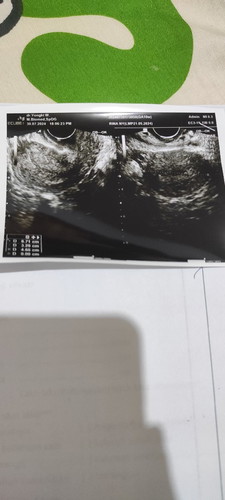

HPHT 21 mei Kata bidan sudah masuk usia 10 minggu. Tp pas di usg kenapa blm muncul kantong dan janin

hasil tepek bagaimana bun?? apakah positif ? jika positif garis 2 jelas.. mending usg lagi ganti dokter . Pake transvaginal ya bun,, klo ttp tidak ada bilang ke dokternya gini "coba dok cari lagi di kiri kanan bagian tuba takutnya hamil diluar kandungan" karna kan harusnya sudah ada klo udh 10 mg

tespek terang sekali bun. itu udh usg biasa sm transvaginal.ttp g keliatan bun. dsuruh balik 2 Minggu lg. tkunya bru terjadi kehamilan ktnya

itu sy usg di dokter obgyn bun. g keliatan apapun

udh dua²nya bun ttp g kelihatan